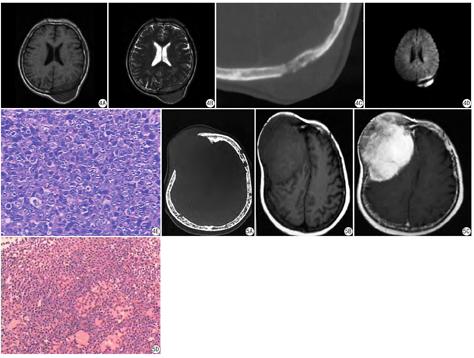

7例侵袭性脑膜瘤CT表现为颅板骨质破坏不一,颅骨增生硬化改变,2例骨质明显破坏,可见残留骨或钙化灶,颅内外板边缘不光整,周围可见较大软组织肿块,MR呈等T1、偏高T2信号,边界多较清,增强检查均有较明显强化,并有脑膜尾征(图1)。8例转移瘤,4例颅骨溶骨性骨破坏,范围较大,2例呈虫蚀状骨质破坏,破坏较小,无硬化边,边缘不清;周围均可见较大软组织肿块,呈稍长T1长T2信号影,增强呈中等强化;1例可见结节样强化(图2),1例累及颈静脉孔。6例嗜酸性肉芽肿CT表现为颅骨局部缺损,由稍高密度软组织肿块代替,范围较小,呈边缘整齐的穿凿样骨破坏,周边可见轻度硬化,膨胀不明显,见"双边征"(颅骨内外板破坏范围不一致)(图3),1例见斑点状死骨,MR病灶呈现长T1长T2信号,增强明显强化,3例见脑膜尾征,1例见结节环形强化,1例周围脑组织大片水肿灶,2例为2个病灶。3例淋巴瘤CT表现为虫蚀状溶骨性改变,骨皮质改变较轻,骨膜反应无或轻,无钙化灶,MR呈稍低或等T1等或稍高T2,1例磁共振扩散加权成像(diffusion weighted imaging,DWI)呈明亮高信号(图4),病灶周围均见有较大的软组织肿块。1例浆细胞瘤,颅骨骨质破坏明显,范围大,周围无硬化,见"双边征",跨颅板内外软组织肿块,呈等T1等T2信号,脑膜增厚,强化明显,颅骨板障内可见多发小病灶(图5)。